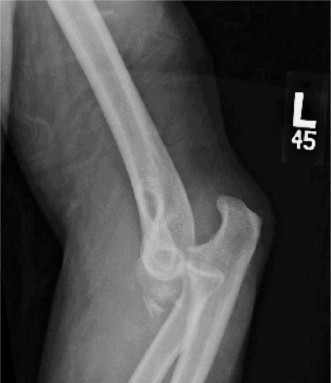

Imaging should include x-rays, which may demonstrate posterior glenoid bone loss or an impaction fracture on the anterior-superior humeral head (Fig. 2–38). CT images with 3D reconstructions can be very useful when assessing the extent of glenoid bone loss and evaluating glenoid and humeral version. Normal glenoid version is from −2 to −8 degrees of retroversion, and this may be increased in posterior instability. MRI can also be useful when assessing the posterior labrum (Fig. 2–39).

Figure 2–38 Radiographs showing a posterior shoulder dislocation.